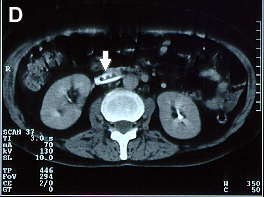

Imagens tomográficas da paciente após a trombose da veia cava inferior. Nota-se a sequência de A para E em que se vê a veia cava normal ao nível das veias renais e abaixo do clipe a veia cava trombosada (aumento do volume com forma circular e halo com captação de contraste)